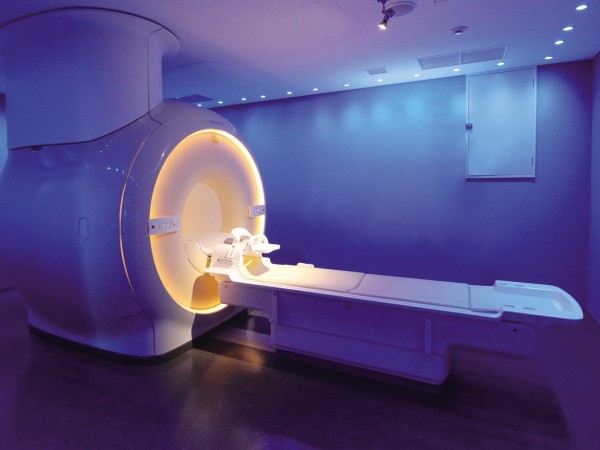

記事をもっと見る 2024年1月25日倉敷中央病院との連携した「先制医療」。VIP専用の予防医療プログラム

2024年1月25日倉敷中央病院との連携した「先制医療」。VIP専用の予防医療プログラム

閉所での不安や窮屈感を解消するMRI検査装置を導入。広い検査空間とバーチャル映像の投影により快適さが向上している。 人生を…